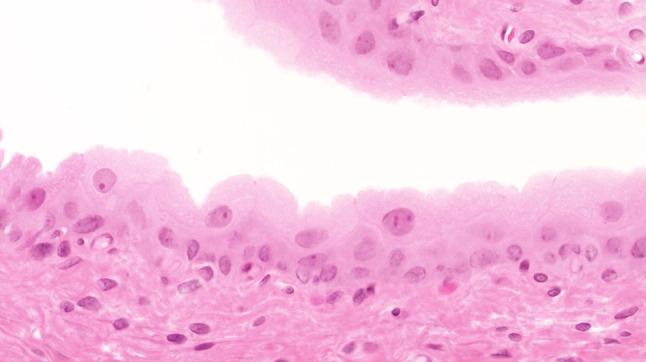

The morphology of experimentally induced urinary bladder precancerous lesions has been differentially interpreted in the literature. Here, we aimed to describe the development of precancerous lesions of the urothelium histologically and by DNA cytophotometric analysis.

We induced precancerous lesions of the urothelium in 60 Wistar rats with 0.05 % N-butyl-N-(4-hydroxybutyl)nitrosamine (BBN) solution as drinking water. After exposure for 2-20 weeks, each animal received tap water for 2 weeks. Subsequently, six animals were killed every 2 weeks, and urothelia of three urinary bladders per time point were examined by DNA cytophotometry of smear preparations. An additional three urinary bladders were processed for histological analysis.

Over 20 weeks, BBN exposure led to a significant difference between the control group and most of the BBN-exposed 2-week groups and to differences between most of these time point groups. After week 4, this difference included a higher proportion of cells with increased nuclear DNA content. At the end of the experiment, DNA cytophotometric values of the urothelium in experimental rats corresponded to those of poorly differentiated urothelial carcinomas.

Biologically significant stages of precancerous lesions were already detectable after 4 weeks of BBN exposure, considerably earlier than previously described in the literature.